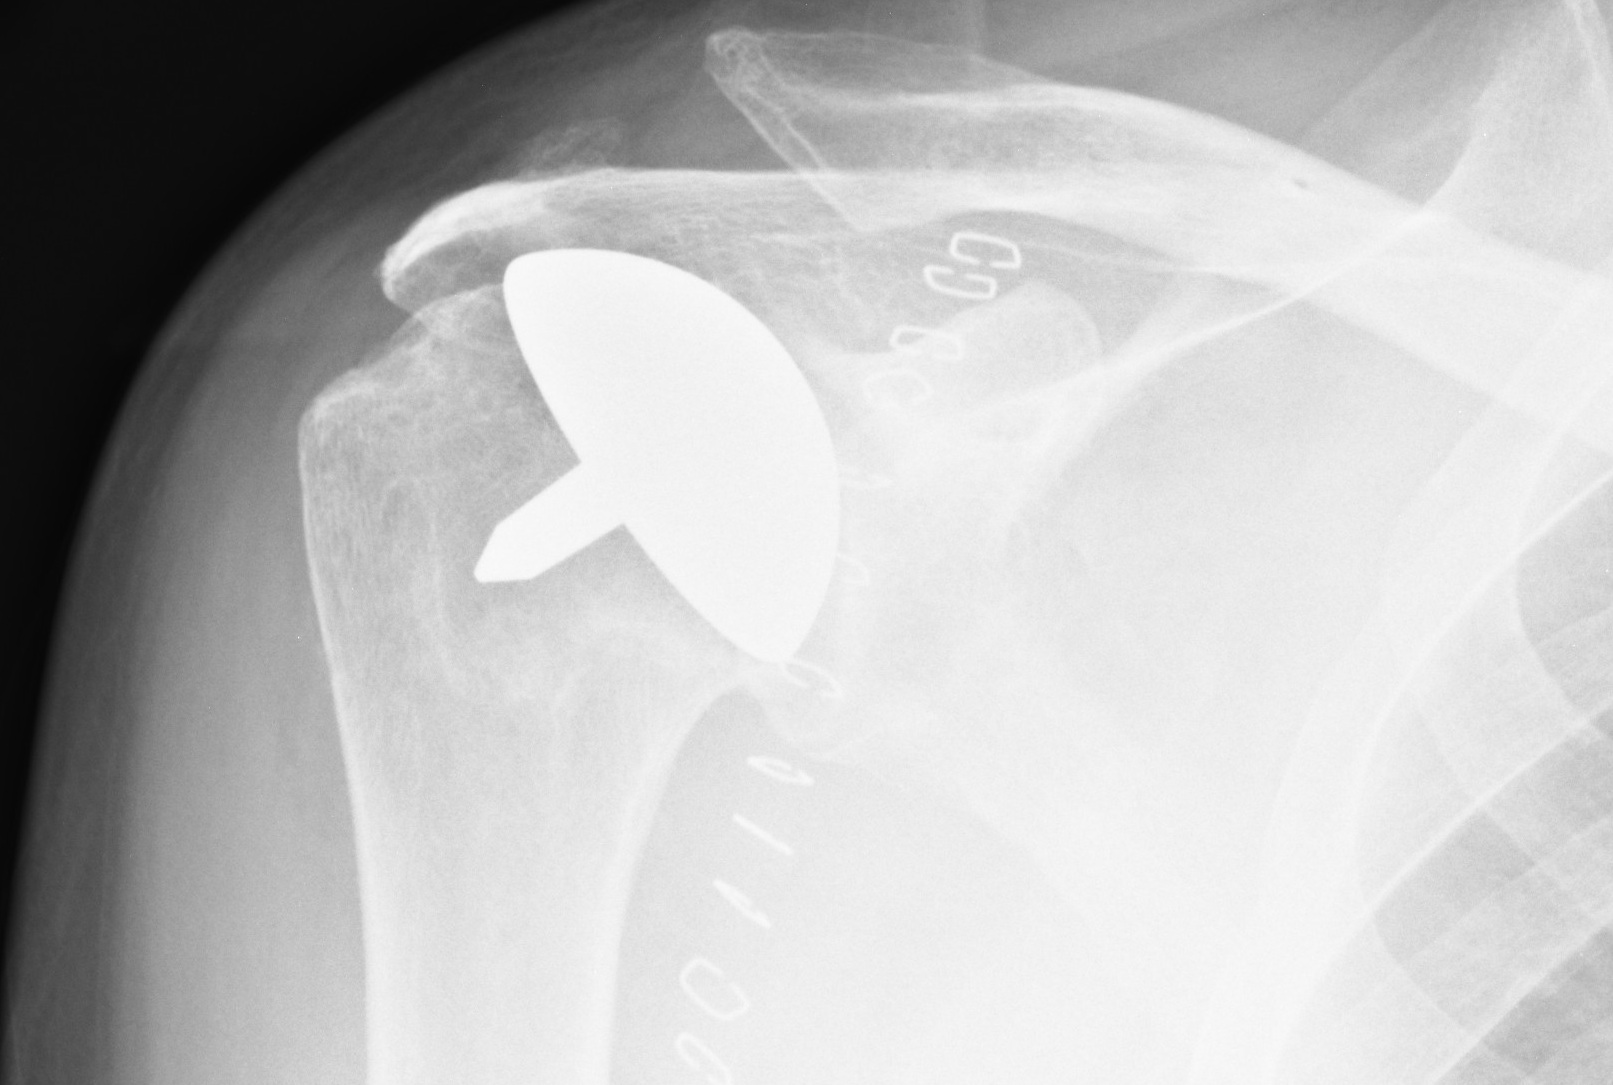

Post operative X-ray showing a resurfacing shoulder replacement